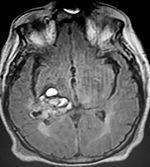

El estudio de RMN presenta una lesión bien circunscrita en hemisferio cerebeloso izquierdo con periferia de predominio hiperintenso en T1 y T2, y centro hipointenso, edema perilesional mínimo, así como una imagen de un vaso venoso alimentador que recorre hacia el ángulo pontocerebeloso izquierdo.

Lesión cerebelosa izquierda ponderaciones en T1 y T2, la flecha señala vaso nutricio hacia el ángulo pontocerebeloso izquierdo, se puede observar el centro de intensidad heterogénea con contenido quístico multiloculado y edema perilesional leve.